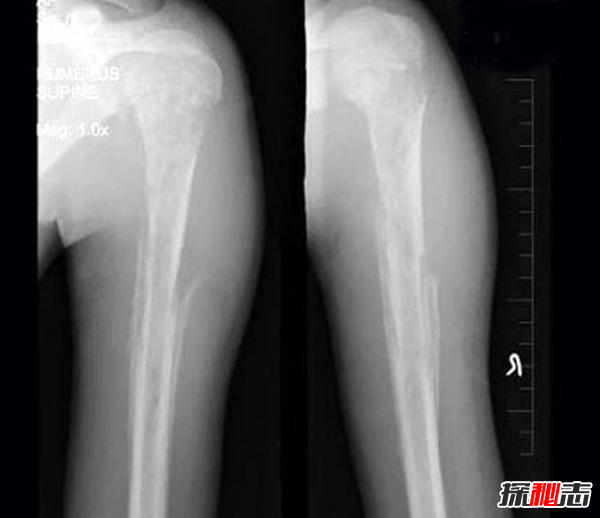

检查:厚皮性骨膜病的X线检查可见胫骨、腓骨、桡骨、尺骨等部位有增生性骨膜炎、弥漫性骨膜增厚。

诊断:根据皮肤及骨骼X线检查见增生性骨膜炎、弥漫性骨膜增厚的典型临床改变可作出诊断。